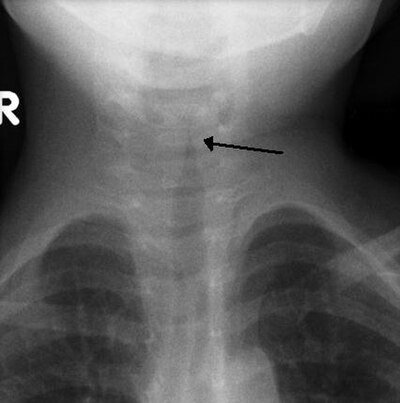

Viral bedingt (Parainfluenzavirus Typ 1–3, seltener RSV, Influenza). Subglottisches Ödem im Bereich des Krikoids — der engsten Stelle des kindlichen Atemwegs.

Alter: 6 Monate – 3 Jahre. Saisonalität: Herbst/Winter. Typische Trias: Bellender Husten + inspiratorischer Stridor + Heiserkeit. Beginn meist nachts. Keine Dysphagie, unauffällige Epiglottis. Symptombeginn allmählich bis 48 Stunden.

Pseudokrupp: bellender Husten, Heiserkeit, mäßiges Fieber.

Epiglottitis: kein Husten, kloßige Sprache, Speichelfluss, hohes Fieber, Tripod.